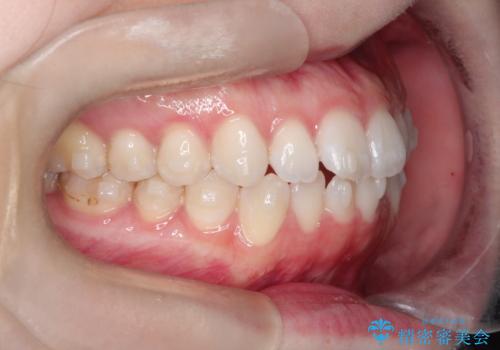

【インビザライン】がたつきをなおしたい

- 上下の前歯の凸凹が気になり、来院されました。

インビザラインで綺麗に仕上がり、満足していただきました。